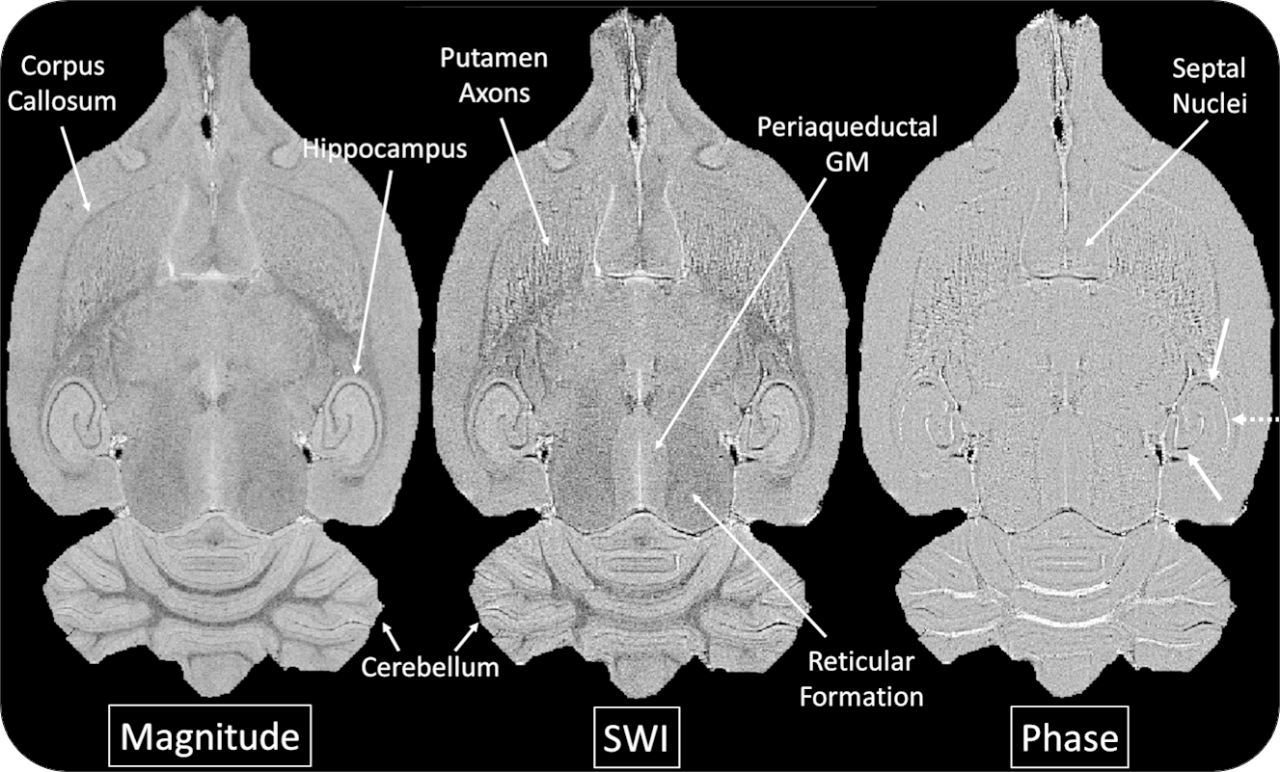

The ultra-high field of the BioSpec 152/11 provides extreme sensitivity for greatest resolution. Its streamlined design for mice studies makes handling simple, while its powerful software guarantees best results. It can be equipped with the MRI CryoProbe to increase sensitivity even further and together with the gradient strength of up to 1000 mT/m, highest resolution is achieved. It is built with nitrogen-free Ultra Shielded and helium Refrigerated (US/R) magnet technology for long service intervals

• Crisp and highly resolved images with native gradient strength of 740 mT/m, upgradable to 1000 mT/m

• MRI CryoProbe for exceptional increase in sensitivity

• ParaVision® 360: intuitive software package, for multi-dimensional MRI/MRS data acquisition, visualization, reconstruction, and analysis

• MRI sequence portfolio of more than 1,000 sequence variations, including wireless cardiac imaging using navigator based IntraGate methods with cartesian or radial readout, as well as short echo time imaging, such as UTE and ZTE